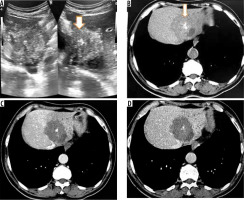

Figure 1

A) Transverse ultrasound image of liver shows a peripheral wedge-shaped hyperechoic mass in segment VII. B) Non-contrast axial computed tomography (CT) image shows wedge-shaped hypodense mass with central calcifications. Post-contrast axial CT image in portal phase (C) and hepatic venous phase (D) does not reveal any enhancement of the lesion. No biliary dilatation or vascular invasion is seen (P1 disease)